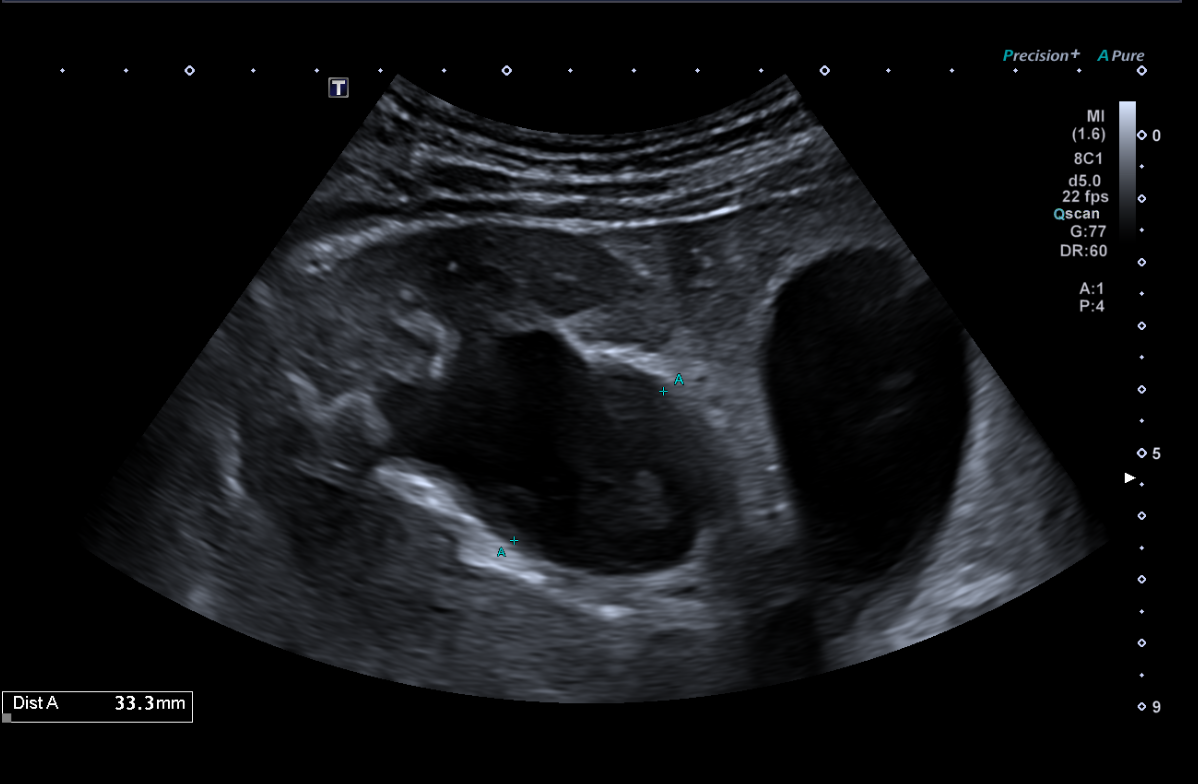

Se establece como hipótesis diagnóstica hidronefrosis. Se plantea como diagnóstico diferencial posible cistitis ulcerativa, así como uropatía obstructiva secundaria a consumo de ketamina. La ecografía clínica resulta determinante para la confirmación diagnóstica, evidenciando datos compatibles con obstrucción de la vía urinaria.

En vista del deterioro de la función renal del paciente, se decide ingreso hospitalario en medicina interna. Se realiza ecografía renal reglada por radiología la mañana siguiente, encontrando hidronefrosis grado III-IV bilateral.